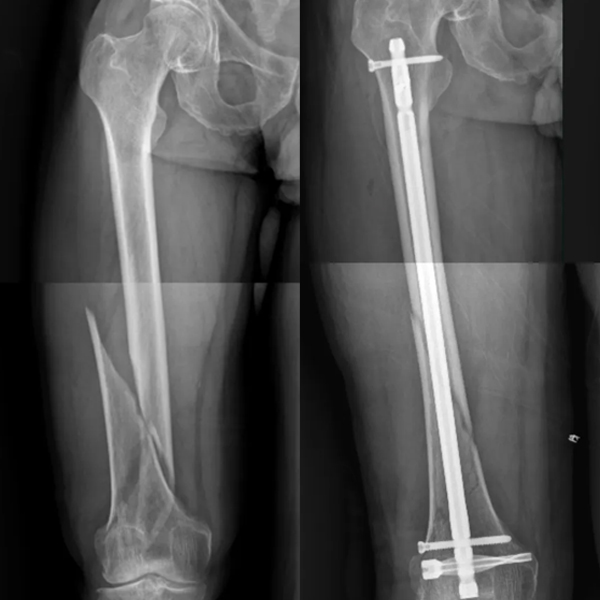

Case1